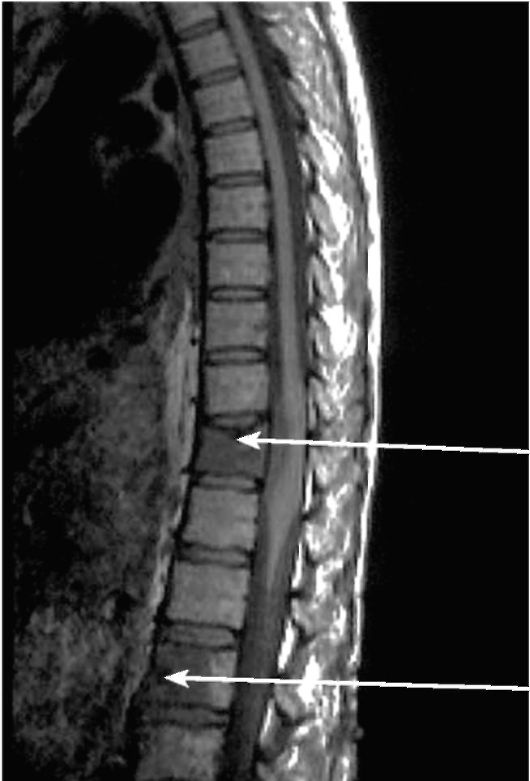

При выявлении множественных поражений костей (чаще всего такая ситуация возникает при поиске скелетных метастазов) велика роль сцинтиграфии скелета (рис. 3-20) и МРТ (рис. 3-21), так как эти методы позволяют выявлять злокачественные поражения костей лучше и на более ранней стадии, чем это делают рентгенографические методы.

Рис. 3-21. МРТ позвоночника при метастазах рака молочной железы (указаны стрелкой